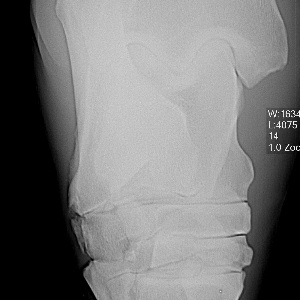

Dr. O - here is the x-ray of the injured leg.Injured Leg

From this small image on my notebook, I think I can see small fragments at the back of the hock. Later I can try to blow it up on my desktop. Are these the only lesions and is the veterinarian recommending removal?

Dr. O. - here is another x-ray (I seem to need to do separate posts):

Another x-ray:

Here is one more x-ray:

An addendum to the above. I have moved the radiograph images to a larger screen and viewing them it appears all the fragments are off the back of the talus and may communicate with the talocaneal joint (correction off the back of the calcaneus and communicates with the talocrural joint~DrO) cand have minimal effect on the stability of the joint. Does the veterinarian who has the originals agree?

Well, Janice you do help buy baby a new pair of shoes but I have to correct my anatomy above, this is most likely off the calcaneus and not the talus and communicates with the talocrural joint not the talocalcaneal joint by way of the proximal intertarsal joint. I must of had talus on the brain. The gist of my comments on prognosis and treatment still apply. I do think a flexed lateral and flexed dorsolateral-posteriomedial and a skyline view of the plantar surface of the talus would further eludicate whether the 4th tarsal bone is involved or intraarticular bone is involved.